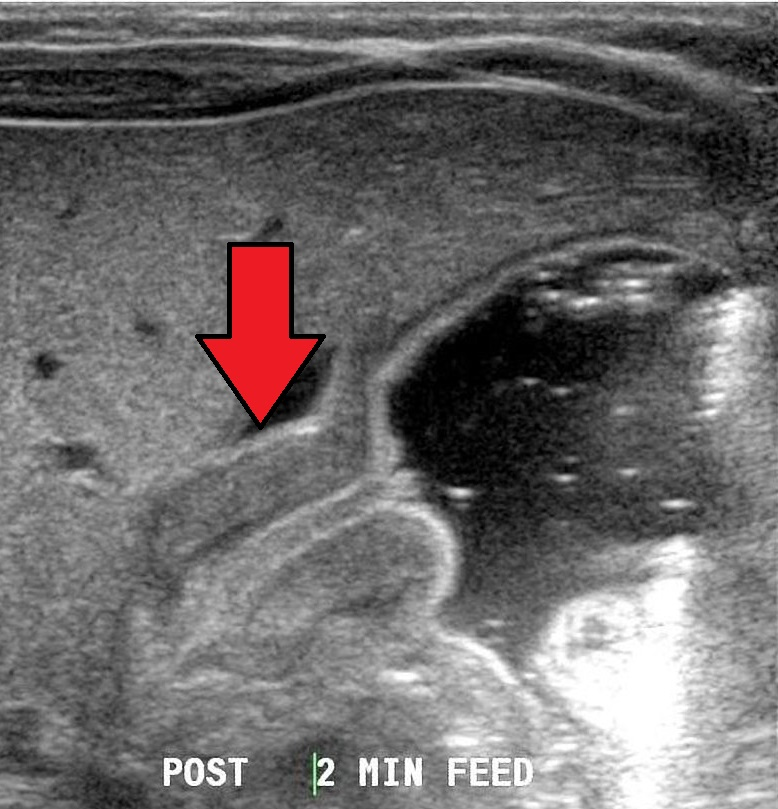

- 복부 초음파: 비후된 유문 괄약근 확인

Pyloric stenosis, Wikimedia Commons